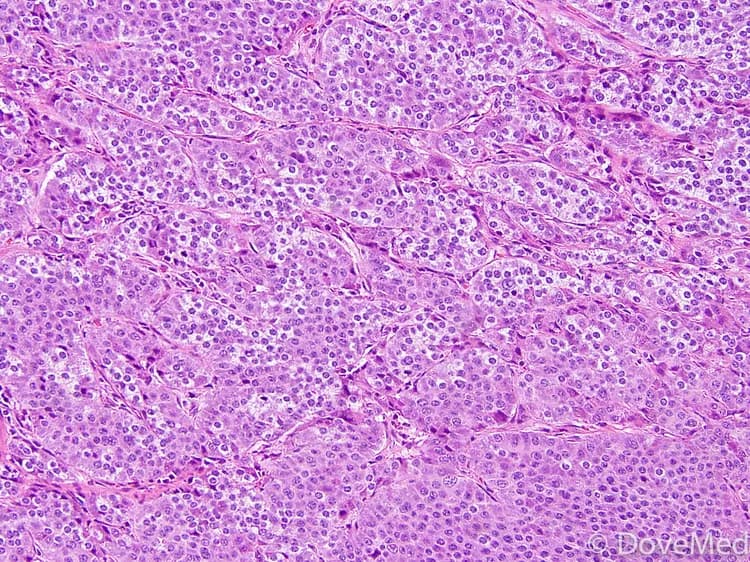

• Atypical Glomus Tumors are classified as tumors that do not have all the criteria of malignancy, but have some atypical features. During a diagnostic of a tissue biopsy by a pathologist, the following features may be observed under a microscope:

• The tumor cells have atypical features in the nucleus

• The tumor has an increased cell division activity (mitotic activity) with atypical mitotic forms

• Parts of the tumor may have a completely benign appearance; this means that the tumor may have a atypical features in one area with some areas that are entirely benign

• Tissue biopsy of tumor specimen:

• A biopsy of the tumor is performed and sent to a laboratory for a pathological examination. A pathologist examines the biopsy under a microscope. After putting together clinical findings, special studies on tissues (if needed) and with microscope findings, the pathologist arrives at a definitive diagnosis. Examination of the biopsy under a microscope by a pathologist is considered to be gold standard in arriving at a conclusive diagnosis

• Biopsy specimens are studied initially using Hematoxylin and Eosin staining. The pathologist then decides on additional studies depending on the clinical situation